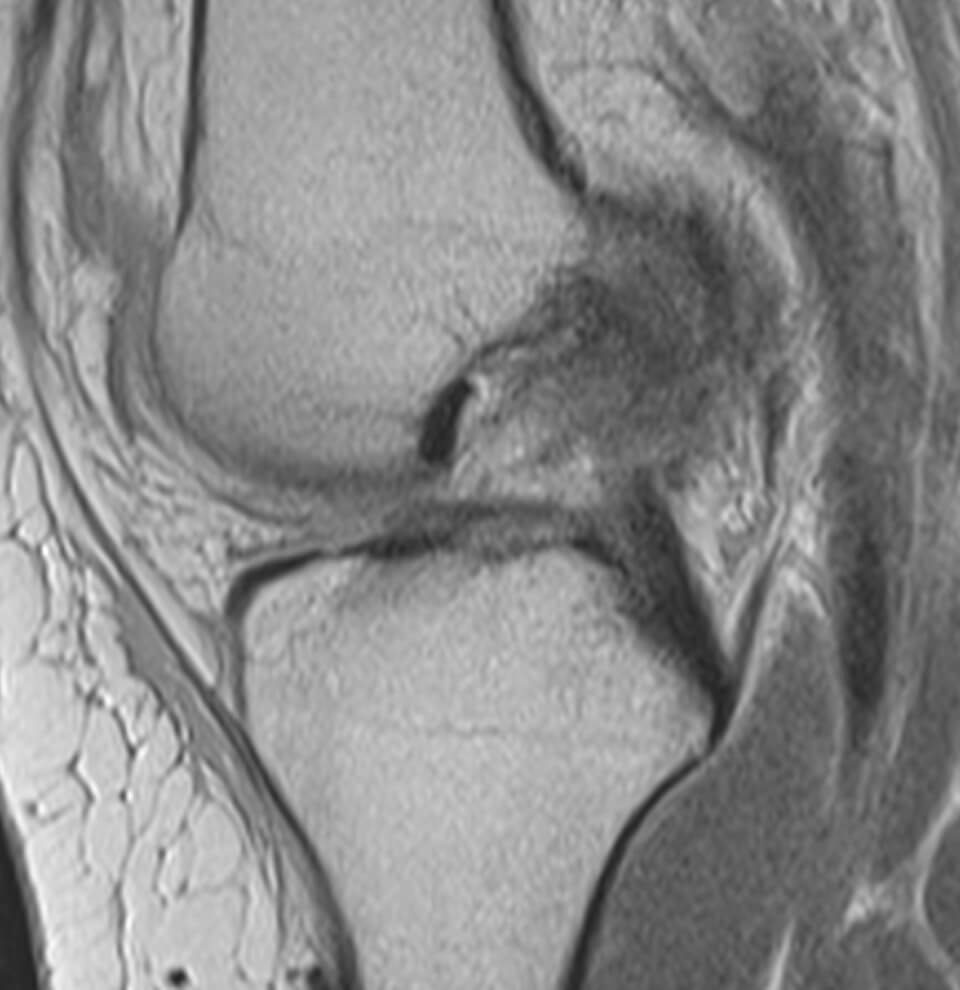

Ο ιατρός θα πάρει αναλυτικό ιστορικό και θα σας εξετάσει προσεκτικά. Μία ακτινογραφία θα αποκλείσει γρήγορα συνοδές κακώσεις των οστών (κατάγματα). Η διάγνωση επιβεβαιώνεται με μαγνητική τομογραφία (MRI), η οποία επιτρέπει την απεικόνιση συνοδών κακώσεων των μαλακών μορίων, όπως κακώσεις έσω πλαγίου συνδέσμου, ρήξεις έξω μηνίσκου ή οπίσθιας και έξω γωνίας. Σημειώνεται ότι η ρήξη μηνίσκου σε συνδυασμό με ρήξη χιαστού είναι εξαιρετικά συχνή.

– Μαγνητική τομογραφία